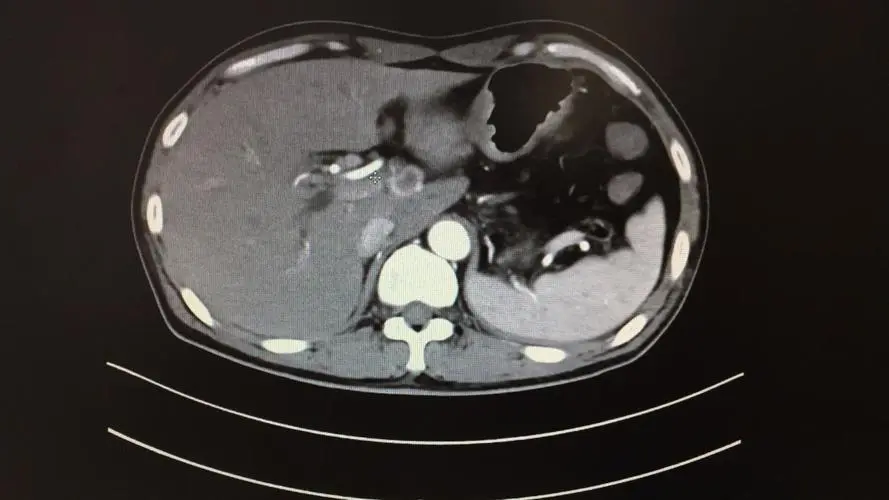

“肝脏占位”是指正常肝脏b超均匀回声或CT均匀密度上 , 肝实质内的异常回声区或密度区 。 简单来说就是肝脏里长了东西 , 占据了正常肝脏的一部分 。

肝脏超声检查是体检或肝病初筛的常用检查方法 。 它可以发现大多数直径超过1cm的肝脏肿块 , 但普通超声无法准确判断肝脏肿块是良性还是恶性 。

也就是说 , “肝脏占位”只是说明肝脏上长了东西 , 至于是“好”还是“坏” , 对健康有没有影响 , 其实都是未知数 。 如果是“好”的 , 也就是良性占位性肝脏 , 大部分余生都不会有任何症状 , 对健康没有影响 。 如果是“坏的” , 即恶性占位肝脏 , 会在短时间内迅速长大 , 破坏肝脏的正常功能 , 甚至转移到身体其他部位 , 对健康造成严重危害;还有少数肝脏肿块属于“不好也不坏” , 即性质介于良性和恶性之间的肿瘤 。 它们的生长速度非常慢 , 可以带着肿瘤活很长时间 。

肝囊肿的病因尚不清楚 , 可能与肝内胆管和淋巴管的发育有关 , 具有先天性和遗传性 。 大多数肝囊肿长时间生长缓慢或几乎不生长 , 只要定期检查超声和肝功能 。 但如果有快速增长或压迫引起的不适 , 则进一步检查 , 如CT、MRI等 。 需要确定是否需要细针穿刺引流、囊肿切除等治疗 。